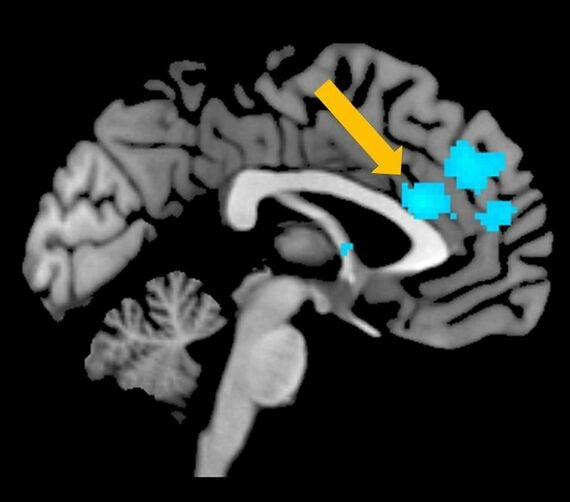

さらに、脳活動を調べてみると、サイコパス傾向が高い人は、前部帯状回と呼ばれる、認知的な葛藤の処理に関わるとされる部分の活動が低いということもわかってきました。

例えば、「1人の命を犠牲にしてでも、5人を助けることが正しいかどうか」というような質問をされると迷うものですが、そういった高次な迷いや葛藤が起きた際に活動するのが、前部帯状回です。

ところが、サイコパス傾向が高い人は、おそらくは道徳的な葛藤が生じていないために、自分がウソをつこうか、つくべきではないかと判断するときに、本来活動すべき前部帯状回の活動が低いわけです。

そのために、通常なら葛藤して時間がかかるようなプロセスであっても、ためらいなくウソをついてしまう仕組みになっていると考えられます。